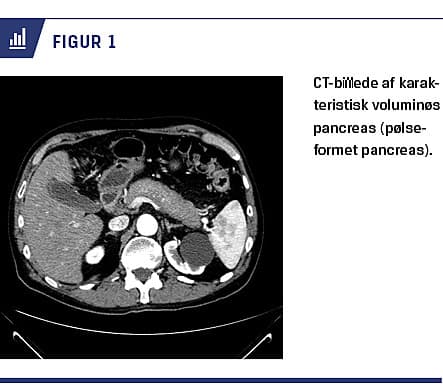

Ved billeddiagnostik ses der hos 40-60% af patienterne typiske forandringer, som karakteriseres af diffus forstørrelse af hele pancreas og forsinket opladning. Dette kaldes også en pølseformet pancreas (Figur 1). Hos 12-40% ses der endvidere en kapsellignende afgrænsning mod det omkringliggende væv – en halo. Atypiske forandringer ses hos 30-40% og kan være enten fokale eller multifokale. Oftest er disse forandringer lokaliseret til caput pancreatis og kan til tider være svære at differentiere fra pancreascancer. Endelig vil der være karakteristisk opladning i de forskellige faser. Ovenstående kan visualiseres ved CT, MR-skanning og PET [5, 19, 20]. UL-skanning af abdomen er mindre specifik, men kan dog bruges til påvisning af en hypoekkoisk diffus forstørret pancreas [5].